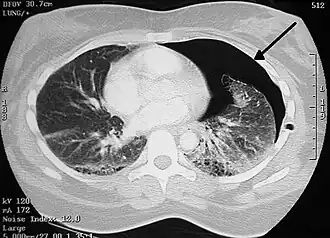

Computed tomography

A CT scan is not necessary for the diagnosis of pneumothorax, but it can be useful in particular situations. In some lung diseases, especially emphysema, it is possible for abnormal lung areas such as bullae (large air-filled sacs) to have the same appearance as a pneumothorax on chest X-ray, and it may not be safe to apply any treatment before the distinction is made and before the exact location and size of the pneumothorax is determined.[18] In trauma, where it may not be possible to perform an upright film, chest radiography may miss up to a third of pneumothoraces, while CT remains very sensitive.[21]

A further use of CT is in the identification of underlying lung lesions. In presumed primary pneumothorax, it may help to identify blebs or cystic lesions (in anticipation of treatment, see below), and in secondary pneumothorax, it can help to identify most of the causes listed above.[18][22]